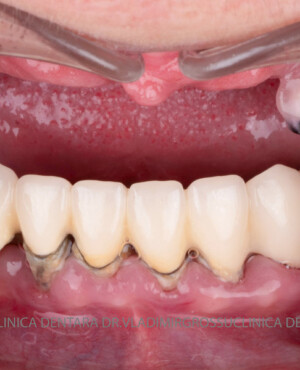

Caz 2